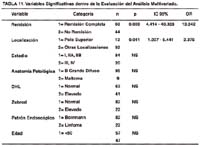

En la Tabla N° 11, se aprecia los resultados del análisis multivariado con el test de regresión de Cox, luego de haber ingresado todos aquellos factores que influencian la supervivencia de los 169 pacientes con Linfoma Gástrico de nuestro estudio, podemos observar que sólo dos variables tienen significancia cuando se utiliza el modelo de regresión de Cox, estos son: la variable de la remisión y la variable de la localización, que tienen una alta significancia estadística y se encuentran dentro de la ecuación de dicha función. De ambos valores, la remisión tiene un OR de 13.342, lo que significa que el riesgo de fallecer por enfermedad cuando no hay remisión de la misma, es 13 veces mayor respecto a aquellos pacientes que si presentan remisión de la enfermedad. De la misma manera, en la localización el OR es de 2.375, esto quiere decir que el riesgo de fallecer por la enfermedad es el doble para aquellos pacientes que presentan localización en el polo superior gástrico respecto al resto de localizaciones.